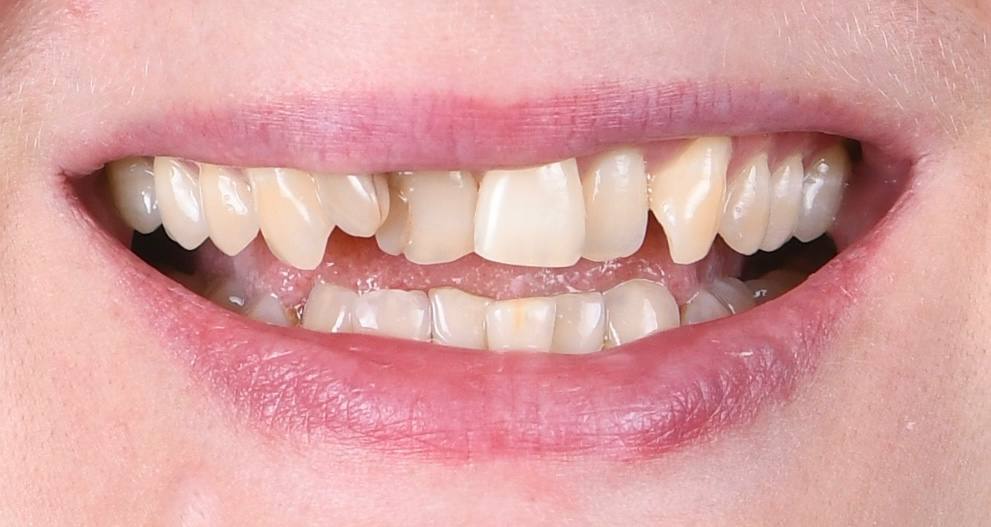

Непростая ситуация, связанная с расположением зубов: лечение кариеса до начала ортодонтического лечения проведено максимально эффективно. Профессионалы своего дела!

Стеснялась улыбаться, потому что один зуб был как будто спрятан назад и казалось, что его нет. Сейчас я счастлива, что могу уверенно улыбаться и моя улыбка мне нравится!